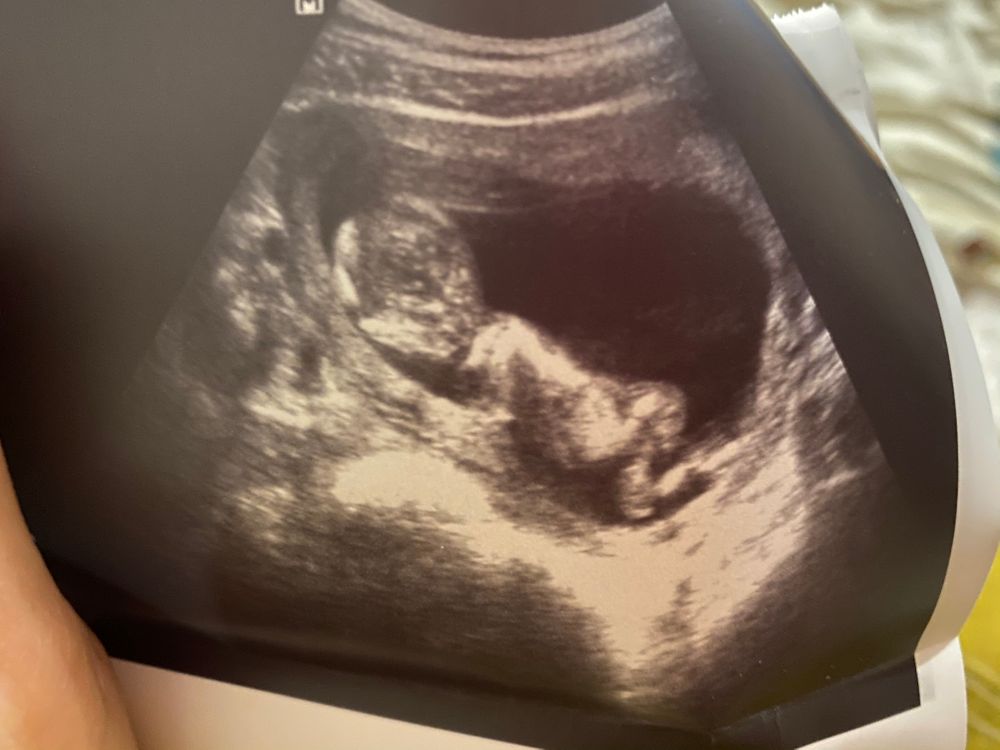

Пол малышаВидела , что некоторые мамочки со стажем, как-то определяют пол по профилю ребёнка на узи ))

Как думаете кто, и почему ?😁

Мне тут девочки все мальчика увидели 100%))) А это пуповина оказалась, поэтому у нас девочка))

В дневнике у вас конкретный мальчик, там даже разглядывать ничего не надо. Девочки выглядят иначе)